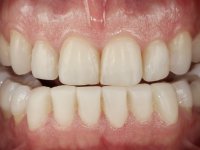

Paciente do sexo masculino, com 36 anos, não fumador. Fez tratamento ortodôntico e reabilitou esteticamente o sector anterior com restaurações em resina composta. As restaurações apresentavam um aumento vertical médio de 2 mm em relação o bordo incisal. Apresentavam-se esteticamente satisfatórias, mas com algumas fraturas incisais. O dente 1.5 apresentava um processo apical e o dente 2.6 apresentava tratamento endodôntico e uma lesão endo-periodontal. No maxilar inferior no local do dente 3.5 apresentava um implante com uma coroa aparafusada e o dente 8.5 ainda estava presente em boca com agenesia do dente 4.5. O paciente apresentava uma ligeira perda da dimensão vertical da oclusão provavelmente associada a um visível desgaste das superfícies oclusais. O periodonto era espesso e apresentava uma excelente higiene oral.

Após análise clínica e imagiológica foi proposto ao paciente recuperar a dimensão vertical da oclusão essencialmente à custa de incrementos oclusais inferiores utilizando “overlays” no sector posterior e facetas no sector anterior. A coroa aparafusada sobre o implante 3.5 seria substituída, no sentido de acompanhar este incremento. Na maxila o dente 2.6 teria extração indicada e posteriormente seria reabilitado com um implante e respetiva coroa. No sentido de reabilitar esteticamente o paciente duma forma minimamente invasiva, foi proposta a colocação de facetas feldespáticas no sector antero-superior. O objetivo de aumentar ligeiramente a D.V.O., teria como função “proteger” eficazmente o sector antero-superior.

Realizado o diagnóstico e tomada a decisão quanto ao tratamento a executar, tornou-se importante definir qual a sequência de trabalho a adotar no sentido de conseguir a reabilitação da D.V.O. (V.D.O), de forma progressiva e equilibrada. Na primeira fase fez-se uma pré-impressão da arcada inferior com silicone tipo “putty” e em seguida realizou-se o preparo dentário de todo o sector posterior. O preparo para os overlays foi feito coronalmente à linha amelo cementaria no sentido de ser o mais conservador possível. A impressão foi feita com técnica de dupla mistura após afastamento gengival realizado com pasta de caulino. A provisória foi realizada com resina composta de polimerização dual. Em laboratório foram realizados os overlays após se ter aberto ligeiramente (1,5mm) a D.V.O. nos modelos montados em articulador semi-ajustável. Simultaneamente o sector antero-inferior foi encerado no sentido de acompanhar este aumento da D.V.O. Também foi confecionada uma chave de silicone translucido para posterior confeção dos provisórios antero-inferiores. Em boca foi primeiro realizada a provisionalização dos dentes anteriores utilizando resina composta previamente aquecida após preparação das superfícies dentárias para a adesão. Foi colocado o dique de borracha para promover o isolamento absoluto e posteriormente foram colados os overlays. Em laboratório foi realizada nova chave de silicone para confecionar os provisórios antero-superiores. Seguidamente em boca foram preparados os seis dentes antero-superiores após colocação do fio de afastamento gengival. Feita a preparação adequada das superfícies dentárias foi realizada a impressão com técnica de dupla mistura e a respetiva provisória. Em laboratório foram confecionadas 6 facetas feldespáticas num modelo de trabalho tipo “Geller”. A provisória foi removida e as facetas foram coladas em boca utilizando um isolamento relativo competente. Esta opção foi tomada em virtude de uma prévia experiencia negativa com a colocação do dique de borracha na mandibula. Após a colagem dos laminados antero-superiores foram dadas 12 semanas para avaliar a adaptação do paciente à nova situação e então iniciar a confeção das facetas antero-inferiores. Após colocação do fio de afastamento gengival. foram feitos os preparos dentários adequados e em seguida foi feita a impressão. Também foi feita a preparação do dente 3.4 que, entretanto, tinha sofrido uma fratura do overlay. As facetas e a restauração do 3.4 foram realizadas num modelo de trabalho tipo “Geller”. Após remoção da provisória, as facetas foram coladas em boca, utilizando um isolamento relativo pelas razões apontadas anteriormente. Após colocação do trabalho o paciente foi reabilitado por outros colegas com um implante na zona do 2.6 e substituição da coroa aparafusada sobre o implante colocado no local do 3.5. Posteriormente surgiram fraturas nos overlays dos dentes 4.7 e 3.7 que foram reabilitados com overlays em Zr.